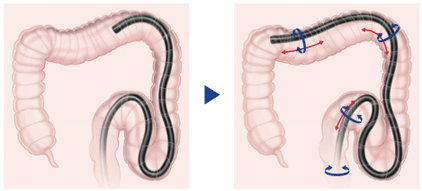

Worm Insertion

Worm Insertion